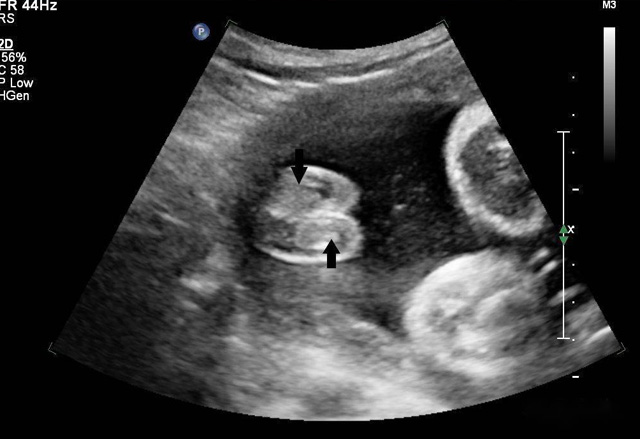

超聲造影

超聲波遇見散射體會發生散射強弱大小,形狀會周圍組織差別、聲阻抗很小散射很微弱,形狀及周圍組織的聲阻抗差別相關。血液內盡管含有紅白細胞、血小板,普通超聲設備沒辦法顯示。人為加入不同介質在血液中增強散射出現雨霧狀的回聲,這就是超聲造影的基本原理。組織對比超聲利用了這一原理。靜脈注射超聲造影劑隨著血液灌流而發展或增強器官和組織的成像,為臨床診斷提供成像數據基礎。